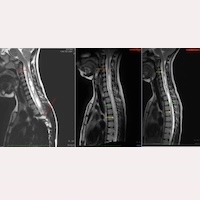

脊髓空洞症